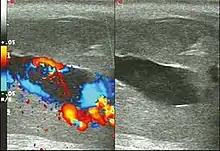

Ultrasonography

Penile ultrasonography with Doppler is the imaging method of choice, because it is noninvasive, widely available, and highly sensitive. By means of this method, it is possible to diagnose priapism and differentiate between its low- and high-flow forms.[11]

In low-flow (ischemic) priapism the flow in the cavernous arteries is reduced or absent. As the condition progresses, there is an increase in echogenicity of the corpora cavernosa, attributed to tissue edema. Eventually, changes in the echotexture of the corpora cavernosa can be observed due to the fibrotic transformation generated by tissue anoxia.[11]

In high-flow priapism normal or increased, turbulent blood flow in the cavernous arteries is seen. The area surrounding the fistula presents a hypoechoic, irregular lesion in the cavernous tissue.[11]